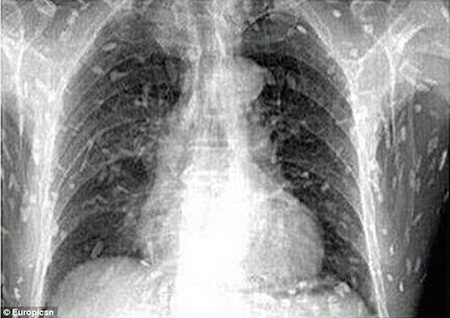

После того, как у него возникли поразительные симптомы, включая расстройство желудка и зудящую кожу, неудачный энтузиаст суши попал в больницу. В Народной больнице Гуанчжоу № 8 в провинции Гуандун он, наконец, получил лечение от заражения лейкемией. Инцидент, безусловно, один для книг, основанный на графических рентгеновских снимках ужасающей болезни. Хотя человек мог умереть от неудачного кризиса здоровья, он получил отличный уход из больницы, а затем выздоровел. Надеюсь, он в следующий раз пропустит сашими.

После употребление сашими, этот человек пошел к своему доктору, жалуясь на боль в животе и зудящую кожу

После того, как его отправили в больницу, выяснилось, что у него была паразитарная инфекция